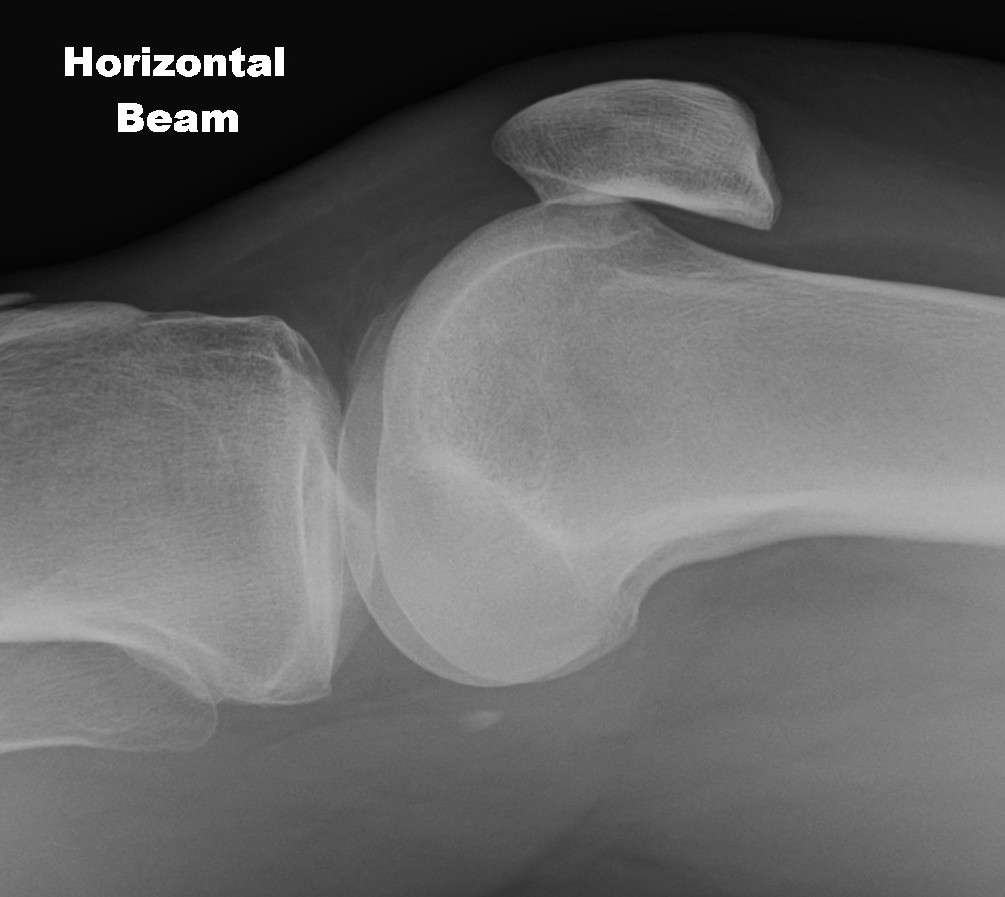

Trochlea Dysplasia / Dejour Crossover Sign

- lateral x-ray at 30o with condyles superimposed

- identify base of trochlea

- normal: clearly defined trochlea groove

- abnormal / Crossover: line of floor of trochlea crosses lateral lip of condyle

Normal trochlea / no crossover